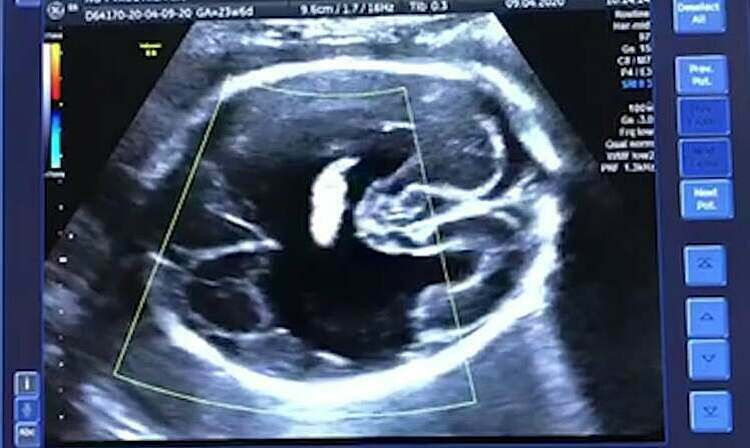

Các xét nghiệm tầm soát dị tật thai nhi lần 1 trong từ tuần 11 đến tuần 13 gồm có siêu âm sàng lọc bất thường nhiễm sắc thể, đánh giá tuổi thai và dự kiến sinh theo chiều dài đầu mông đồng thời chẩn đoán số lượng thai và số lượng bánh nhau, số lượng buồng ối nếu là đa thai.

Bên cạnh đó bác sĩ cũng sẽ quan sát sớm các cấu trúc giải phẫu của thai như tay, chân, thành bụng, tim, hộp sọ, bánh rau... để phát hiện các bất thường lớn của thai cũng như đánh giá khoảng mở trong não (IT) theo tiêu chuẩn FMF để có thể phát hiện sớm dị tật ống thần kinh và sàng lọc nguy cơ tiền sản giật.